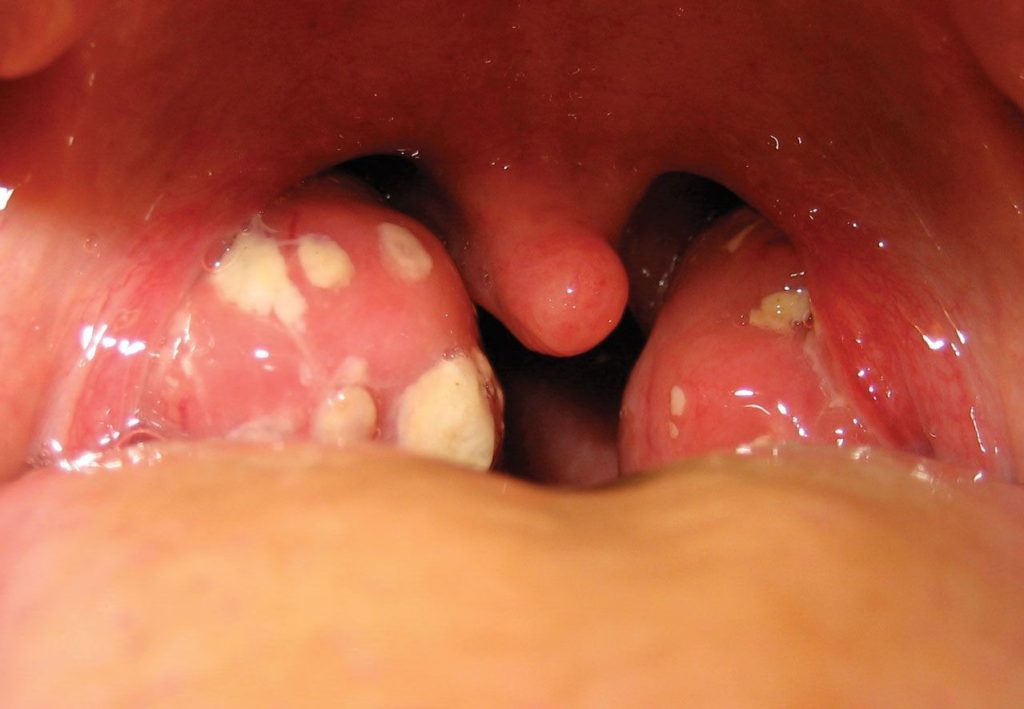

A inflamação persistente nas amígdalas pode ser causada por alguns motivos. No meu caso, descobri que a minha garganta ficava inflamada porque um tipo específico de bactéria não era completamente eliminado. Aí, ela se aproveitava de qualquer resfriado para voltar com tudo. Outra coisa é a formação de “cáseos amigdalianos”, que são aquelas bolinhas brancas que aparecem às vezes. Elas são restos de comida e bactérias acumulados, e podem causar mau hálito e inflamação constante.

Quando a gente fala de sinais de alerta para amigdalite crônica, é importante observar mais do que só a dor. Se você percebe que tem mau hálito persistente, um gosto ruim na boca, inchaço nos gânglios do pescoço ou secreção amarelada/esbranquiçada saindo da garganta, esses são pontos que você não deve ignorar. Esses sintomas podem indicar uma infecção mais estabelecida ou que a inflamação não tá passando sozinha.